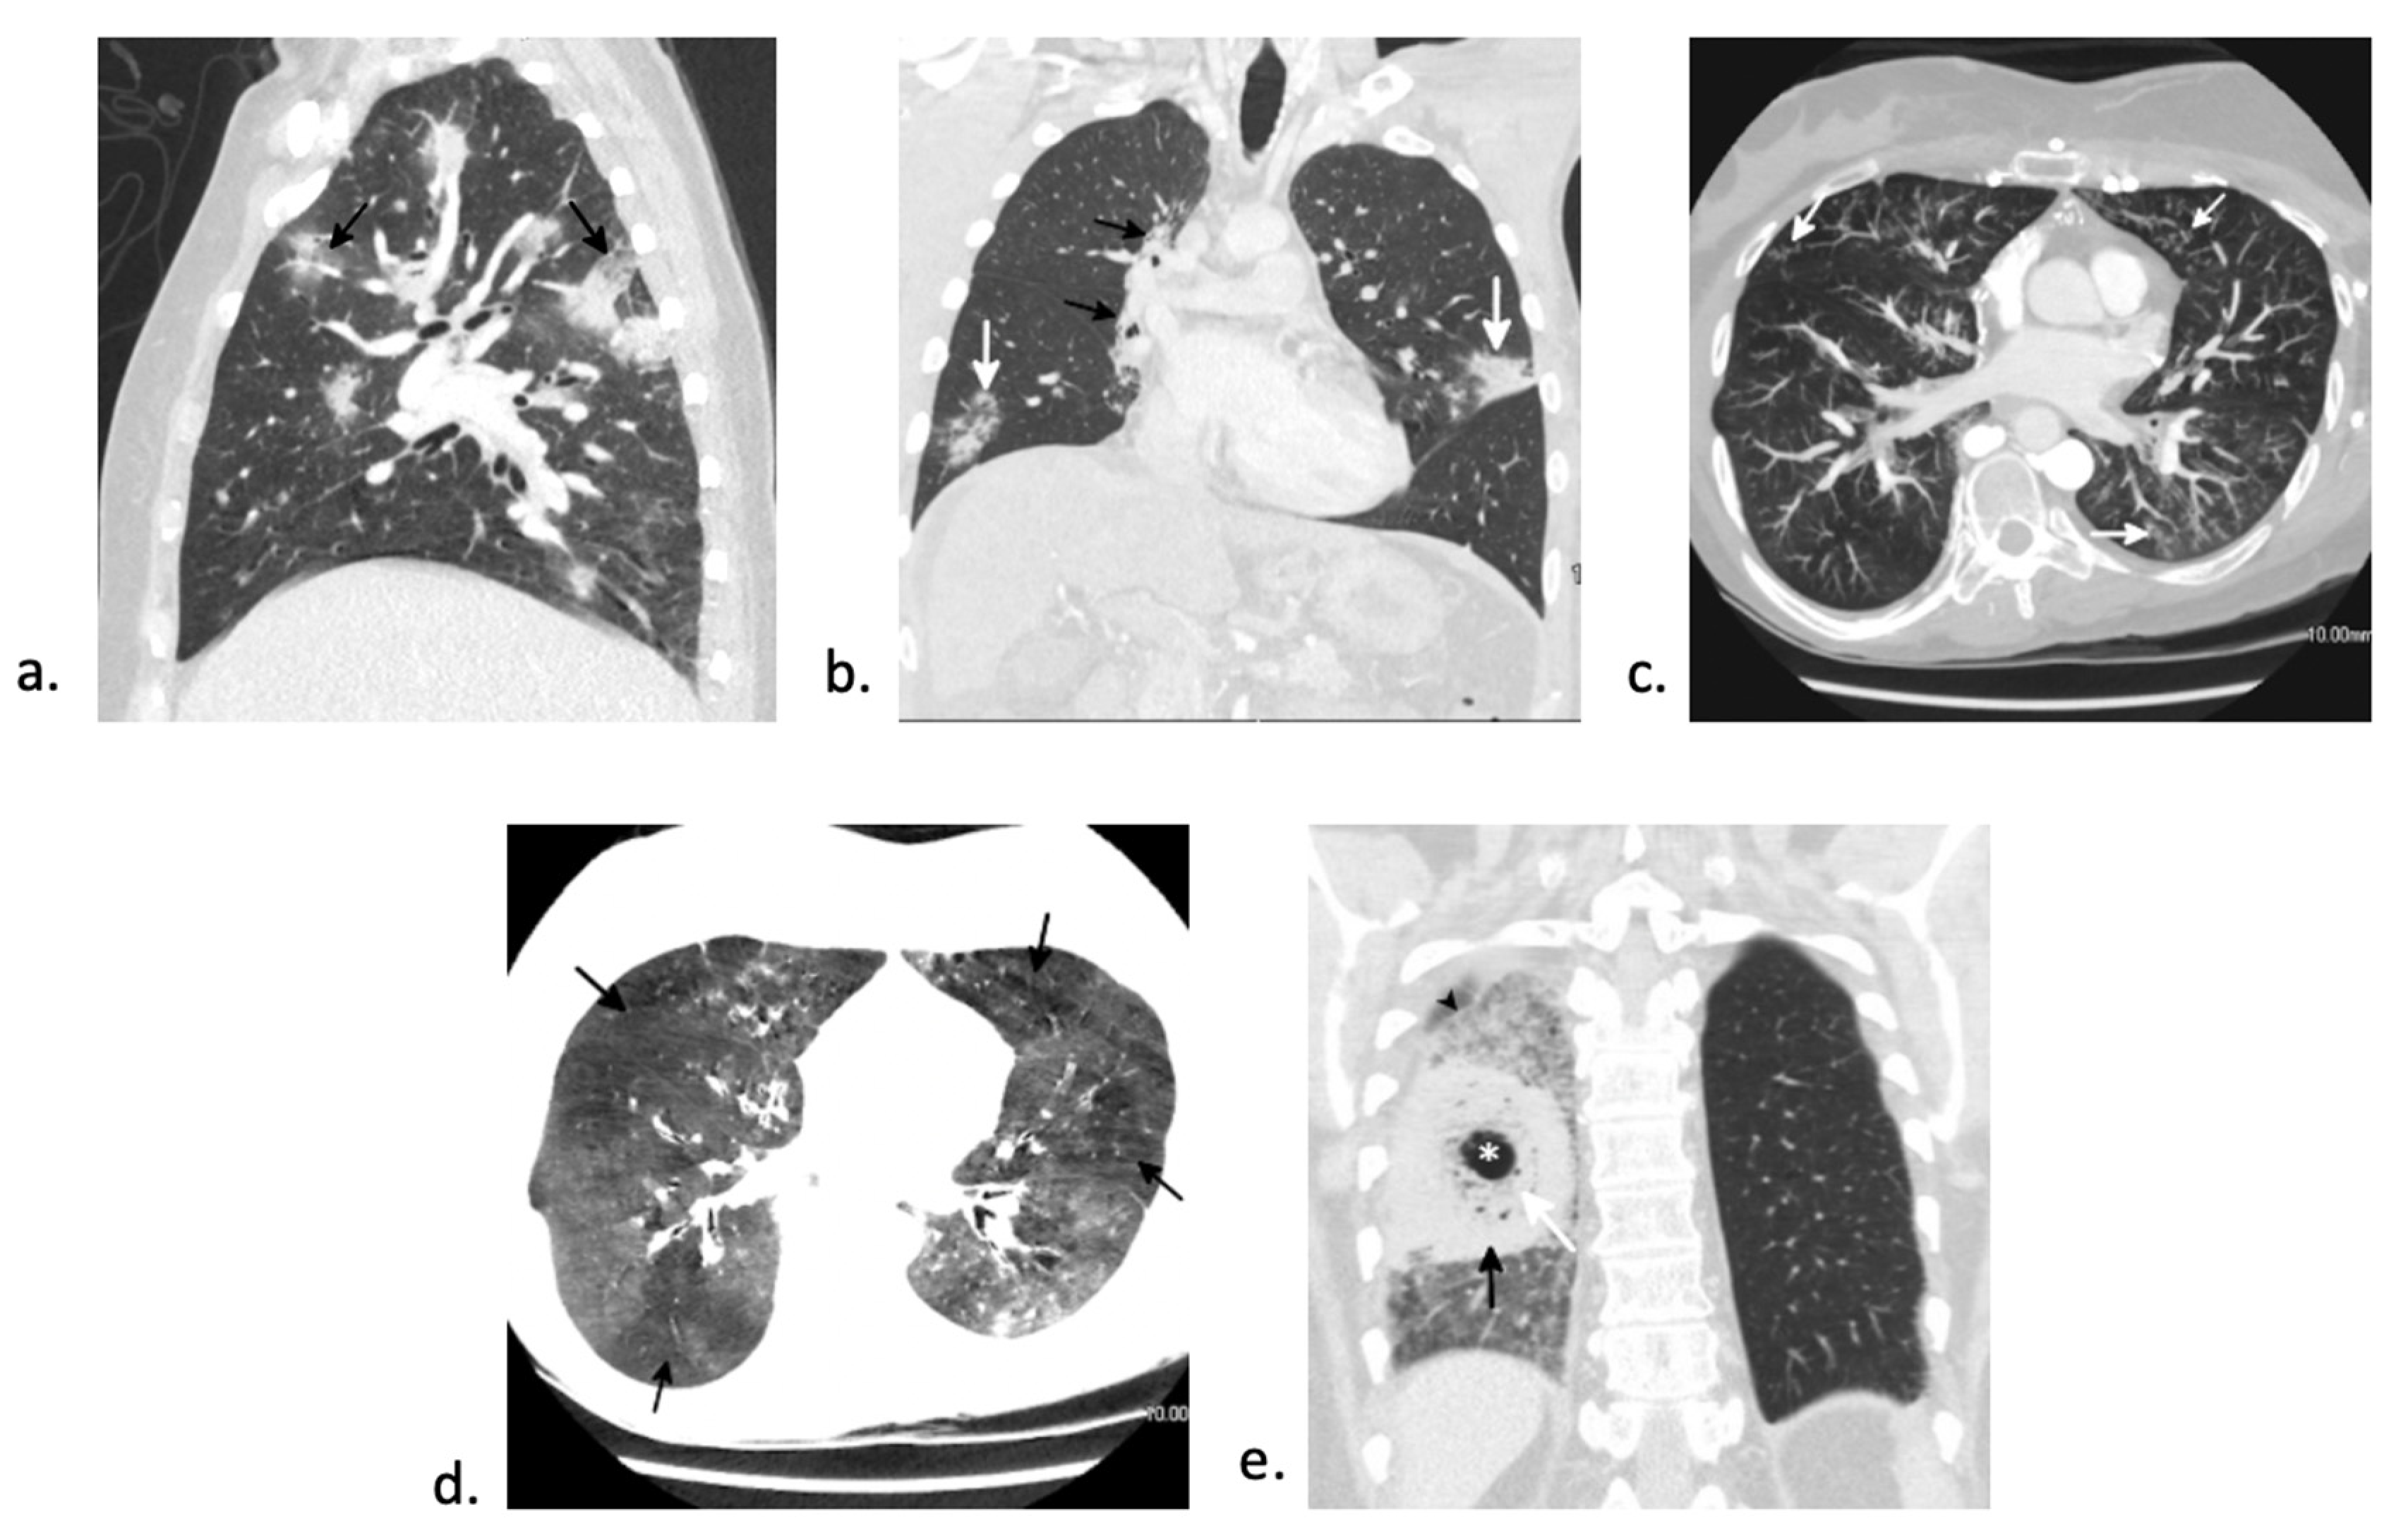

7.2. Fungal Pneumonia

7.3. Viral Pneumonia